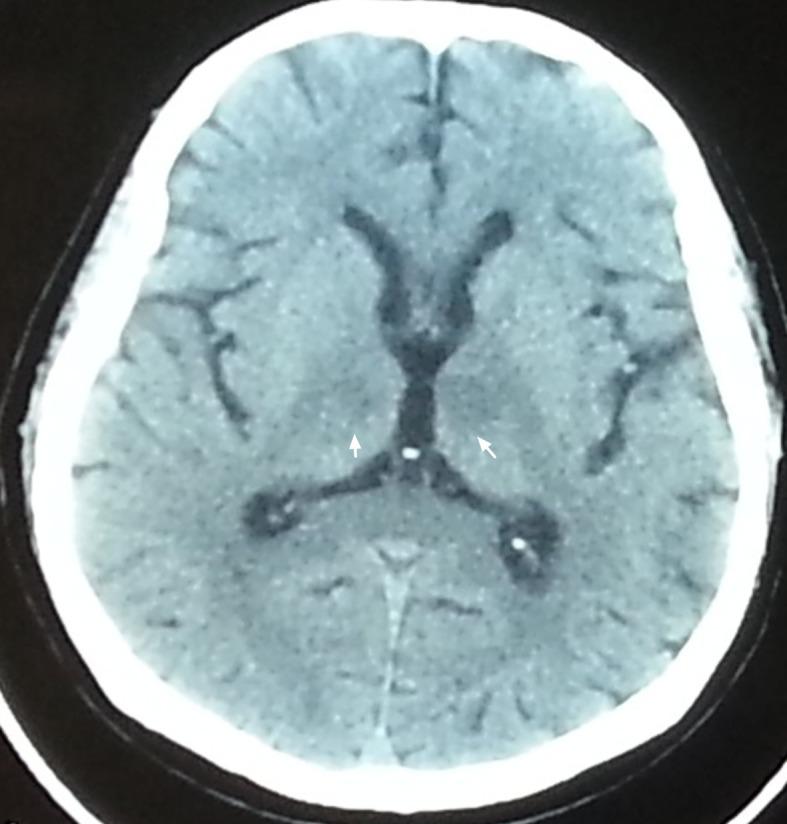

Acute bilateral paramedian thalamic and mesencephalic infarcts are uncommon. Occlusion of the artery of Percheron (AOP) is presumed to cause this specific stroke syndrome. However, occlusion of the AOP is rare and early diagnosis is challenging. Here we described a 70-year-old male patient who presented with acute disturbance of consciousness due to acute bilateral paramedian thalamo-mesencephalic infarction secondary to AOP occlusion. Anticoagulant therapy was administered, and his consciousness gradually improved.

急性双侧丘脑旁正中及中脑梗死并不常见。Percheron动脉(AOP)闭塞被认为会导致这种特定的中风综合征。然而,AOP闭塞很少见,早期诊断具有挑战性。在此,我们描述了一名70岁男性患者,因AOP闭塞继发急性双侧丘脑-中脑梗死而出现急性意识障碍。给予了抗凝治疗,其意识逐渐改善。